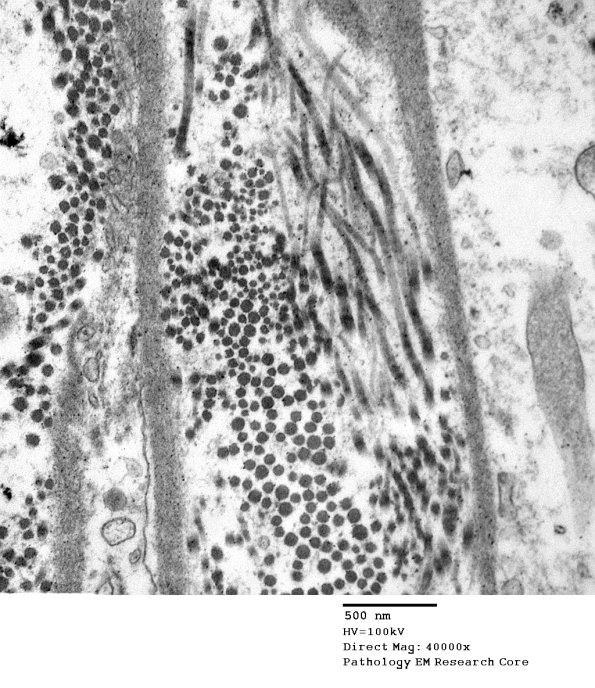

The perineurium is abnormal in a number of ways. In this image the layers of the perineurium are expanded by increased collagen. (electron micrograph)